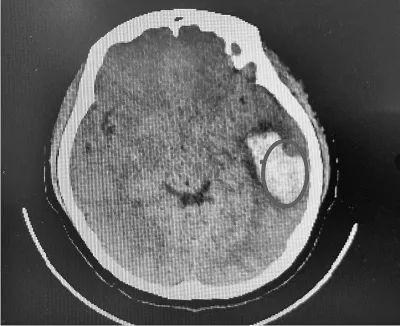

此前,河南一女大学生欢欢(化名)和朋友在KTV唱完一曲《凉凉》之后,感觉到恶心、呕吐、头晕头痛后,被送往医院,经检查后发现为脑出血。

2019年6月18日上午,在郑州大学第一附属医院郑东院区急诊抢救室,20岁的欢欢躺在病床上。虽然入院已经超过36小时,但医生称她还处于危险期。

患者的脑部检查结果

“出血量比较大,有近30毫升。如果未及时就医,后果不堪设想。”医生说,欢欢虽然年纪比较小,症状表现比较轻,但也不能大意。